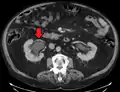

CT scan of bilateral hydronephrosis due to a bladder cancer

Massive hydronephrosis as marked by the arrow.- Renal ultrasonography of hydronephrosis[14]

- Stone causing hydronephrosis[14]

- Urine jets[14]